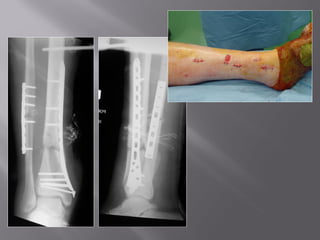

Post-op

5 months